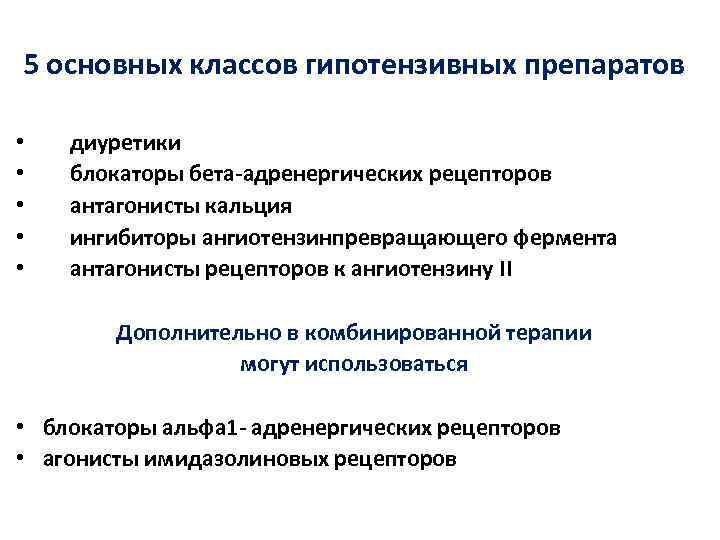

5 основных классов гипотензивных препаратов • • • диуретики блокаторы бета-адренергических рецепторов антагонисты кальция ингибиторы ангиотензинпревращающего фермента антагонисты рецепторов к ангиотензину II Дополнительно в комбинированной терапии могут использоваться • блокаторы альфа 1 - адренергических рецепторов • агонисты имидазолиновых рецепторов

5 основных классов гипотензивных препаратов • • • диуретики блокаторы бета-адренергических рецепторов антагонисты кальция ингибиторы ангиотензинпревращающего фермента антагонисты рецепторов к ангиотензину II Дополнительно в комбинированной терапии могут использоваться • блокаторы альфа 1 - адренергических рецепторов • агонисты имидазолиновых рецепторов